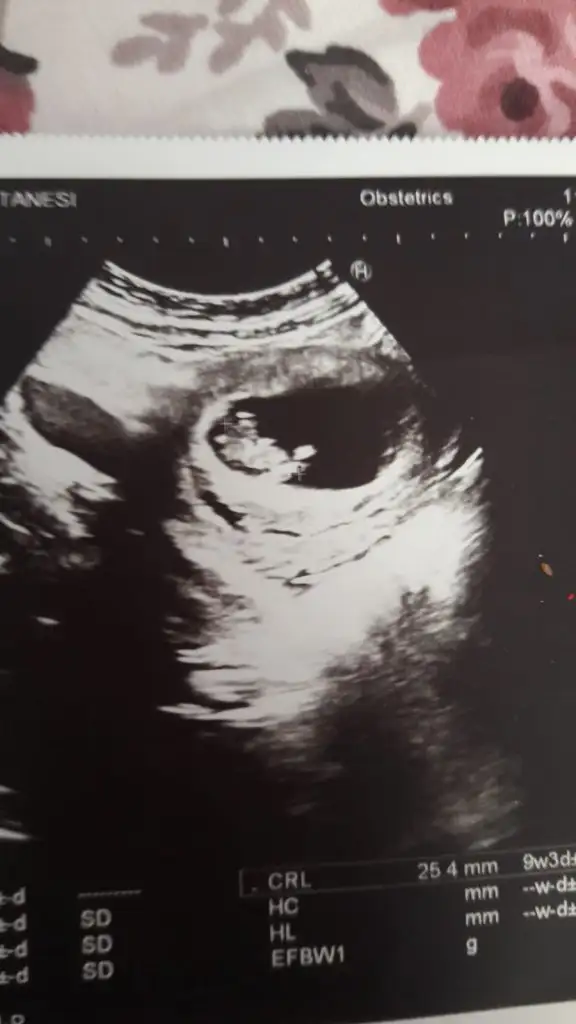

Kaç haftalıkMrb bu arkadaşımın ultrason görüntüsü bakar mısınız